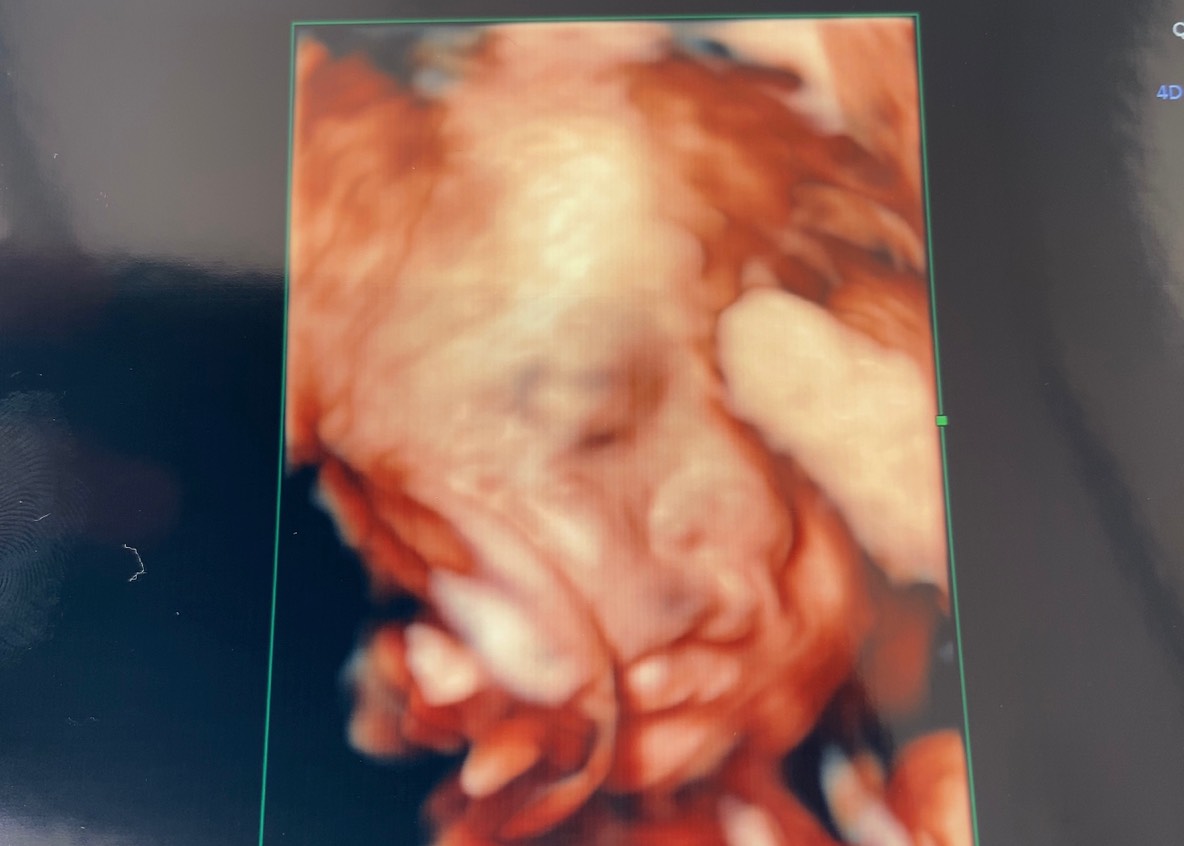

主人似?私似?4Dエコー

この頃になると、赤ちゃんの顔立ちもはっきりし始め、

主人似か私似か分かってきました(笑)

これは・・・

私似だ・・・(笑)

主人にこのエコー写真を見せると、寝ている時の私にそっくりだそうです(笑)

ですが、主人に似てほしい・・・(笑)

でもさすが我が子、可愛いです!!♡(親バカですみません)